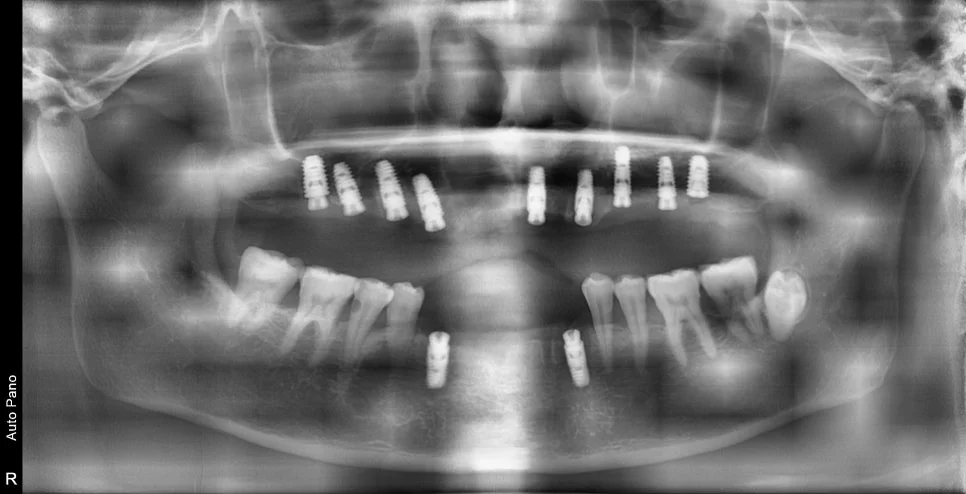

수술 전후 파노라마 비교

CBCT 단면 – 각 임플란트 개별 검증

CT 상에서 하얀색인 임플란트가 1. 온전히 뼈 안에 잠기게(1~2mm 깊게) 그리고 2. 가급적이면 입천장 쪽으로 식립되었다면 잘 심긴 임플란트입니다. (입술 쪽 뼈는 쉽게 흡수됩니다ㅜ)